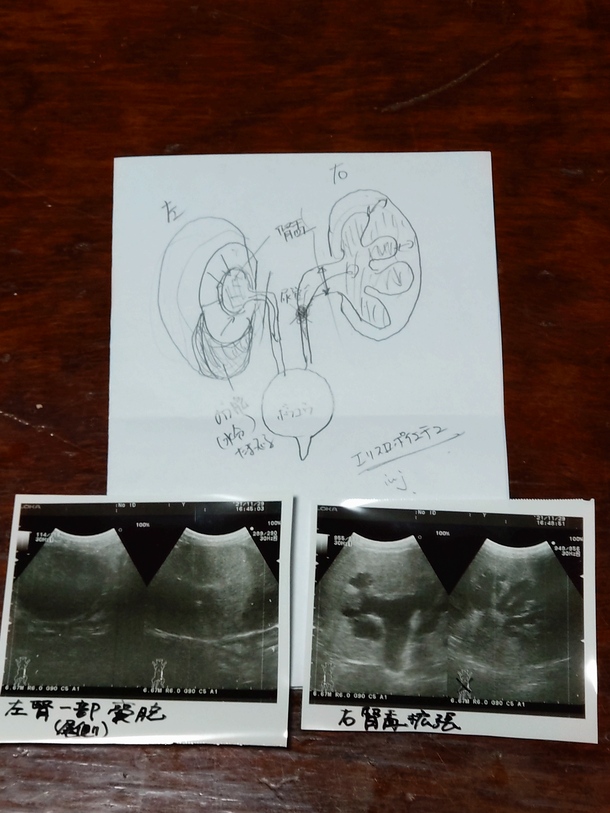

エコー検査~

レントゲン検査~

先生が丁寧に説明して下さり……

今の状態を維持出来る様に、

お薬やサプリ~

ブチャ君💕が続けれる物を模索しながら、病気と付き合って行く事になりました🙇